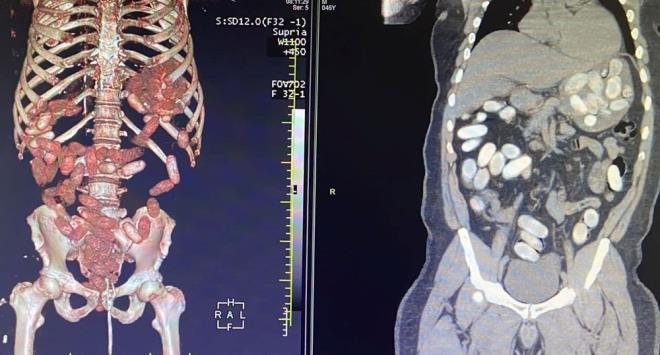

4. Yapılan ön kontrollerde şüphelilerin midelerinde normal dışı bazı materyaller olduğu belirlendi. Gümrük Muhafaza ekiplerince savcılık talimatı doğrultusunda detaylı bilgisayar tomografi çekilmesi için sağlık kuruluşuna götürülen 6 yolcunun yapılan tarama ve muayenelerinde 761 adet ve toplam ağırlığı 10 kilo 420 gram kokain tespit edildi.

Yapılan ön kontrollerde şüphelilerin midelerinde normal dışı bazı materyaller olduğu belirlendi. Gümrük Muhafaza ekiplerince savcılık talimatı doğrultusunda detaylı bilgisayar tomografi çekilmesi için sağlık kuruluşuna götürülen 6 yolcunun yapılan tarama ve muayenelerinde 761 adet ve toplam ağırlığı 10 kilo 420 gram kokain tespit edildi.